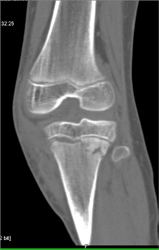

Tibial Fracture